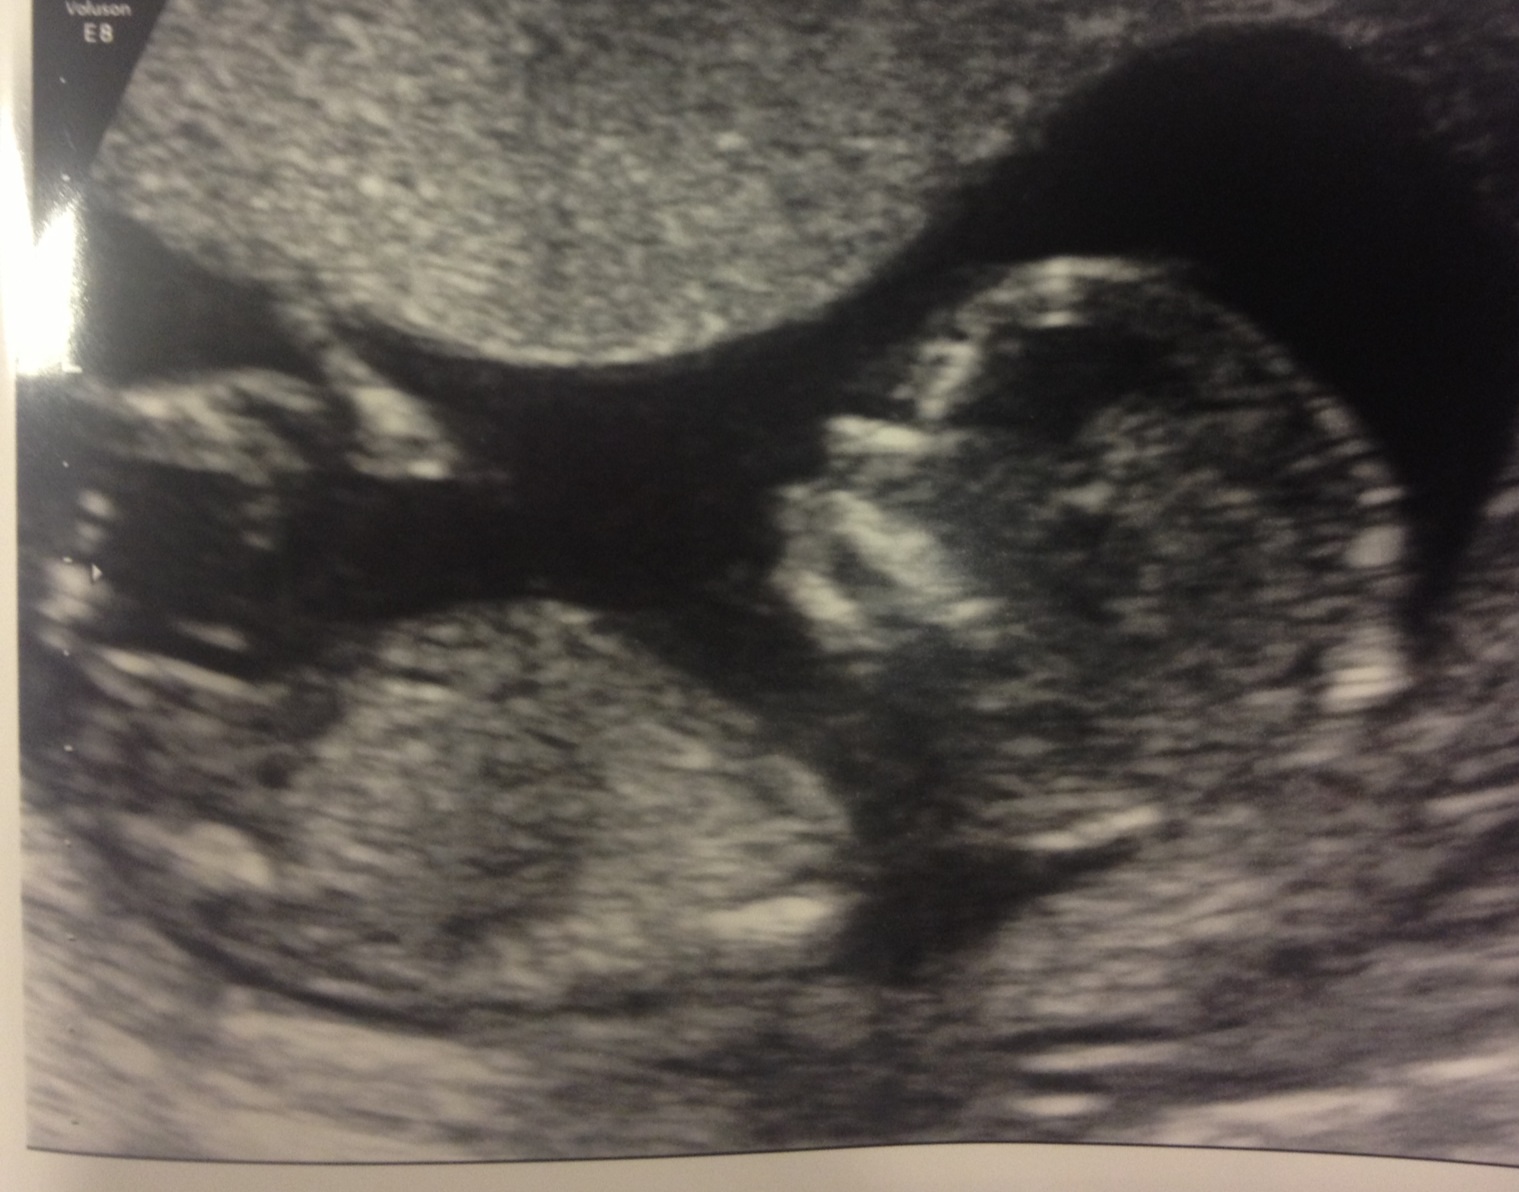

This scan was on 2/17. According to my cycle, the baby is 12w3d. According to a previous dating scan- I am 13w1d during this scan.

13w 1d is that a nub to judge angle of?!

Not sure if what I'm looking at is a nub. Could be part of a leg. If it is a nub, I'd guess girl.

Someone told me that this is the nub. With the arrow pointing to it. Is that kinda long for nub? I guessed part of leg as well.

yes, if that is the nub my guess is girl as well